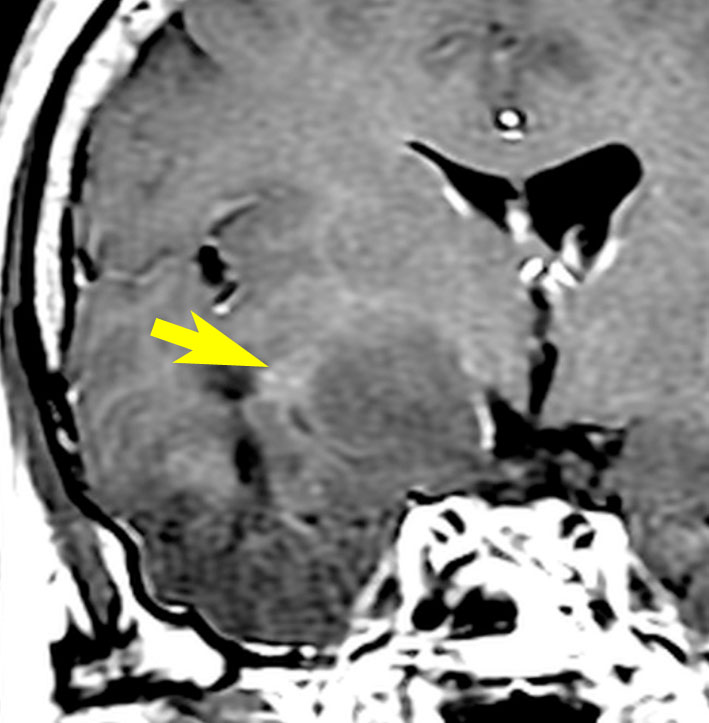

若い成人です,認知機能障害で発症しました。この画像を見るからに悪性神経膠腫,少なくともグレード3のグリオーマであることは明白です。しかし,グレード4膠芽腫あるいはグレード3退形成性星細胞腫にしては腫瘍周辺浮腫が軽すぎます。ですから,グレード3の退形成性乏突起膠腫 AO かも。認知機能の回復と温存を考量して,脳梁損傷と前交連損傷を避けて,右上前頭回と帯状回腫瘍を摘出しました。

左は術後のT1強調ガドリニウム増強像で,残存腫瘍がわかります。この腫瘍に対してICE (IFO/CDDP/VP-16) 化学療法を1コースしました。右側のMRIが1ヶ月後の画像です。このように1p/19q欠失のある退形成性乏突起膠腫は,化学療法感受性がとても高い悪性グリオーマです。ですから,手術で後遺症を残さないように,勢い込んで腫瘍を摘出しようとしないことが大切です。光顕診断はAOで,後々の解析で1p/19q codeletion でした。